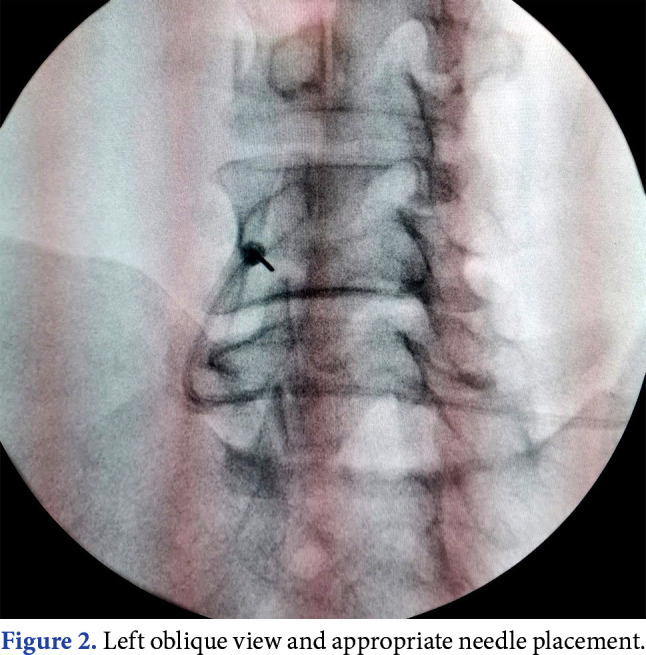

Objectives: This study aimed to compare the treatment outcomes between dorsal root ganglion (DRG) pulsed radiofrequency (PRF) and DRG PRF plus transforaminal epidural steroid injection (TFESI) in patients with chronic lumbosacral radicular pain.

Patients and methods: Eighty-one patients (39 males, 42 females; mean age: 57.5±11.9 years; range 18 to 65 years) who underwent DRG PRF (Group 1) and 59 patients (34 males, 25 females; mean age: 58.7±12.3 years; range 18 to 65 years) who underwent DRG PRF plus TFESI (Group 2) between February 2021 and June 2022 were enrolled in the retrospective study. A Visual Analog Scale (VAS) was used to assess pain severity. Patients in both groups were evaluated before treatment and at four weeks and six months after treatment.